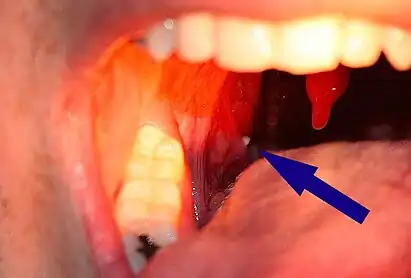

| A tonsillolith lodged in the tonsillar crypt | |

A tonsillolith protrudes from the tonsil